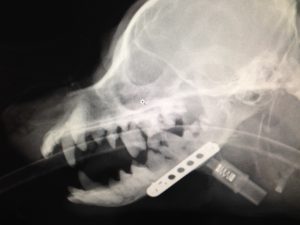

診察すると、下アゴの歯根部が腐り、アゴの骨が溶けて、骨折していました。

約3時間の手術で、チタン合金のプレートを装着。